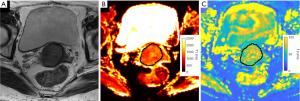

For healthy volunteers, the VOIs of cervical mucosa and stroma were individually delineated on the T1 and T2 maps of MRF1 (Figure 1). The central canal was excluded from the delineation of cervical mucosa. The same procedure was repeated on the T1 and T2 maps obtained from MRF2 (Figure 2). For patients with CC, the VOIs of CC were drawn by strictly delineating the border of CC from adjacent normal tissue on each slice to cover the full extent of the tumours on the T1 and T2 maps (Figure 3).

CC had an average T1 value of 1,529±112 ms and was significantly higher than normal mucosa (P=0.031, compared with MRF1 and MRF2) and stroma (P<0.001, compared with MRF1 and MRF2). CC had an average T2 value of 69±9 ms and was significantly lower than normal mucosa (P<0.001, compared with MRF1 and MRF2). A full tabulation of the T1 and T2 values of CC and normal cervical tissues, as well as the cut-offs, AUC, sensitivity, and specificity, can be found in Table 4 with corresponding box and whisker plots depicted in Figure 7.